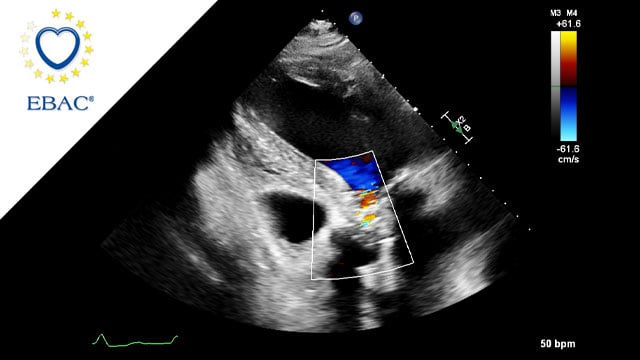

Treating tricuspid regurgitation percutaneously: tools and impacts

19 May 2022 – From EuroPCR 2022

Discover the tools and impacts of treating tricuspid regurgitation percutaneously by watching the cases of valve replacement, valve-in-ring implantation, transcatheter edge-to-edge repair and many more.